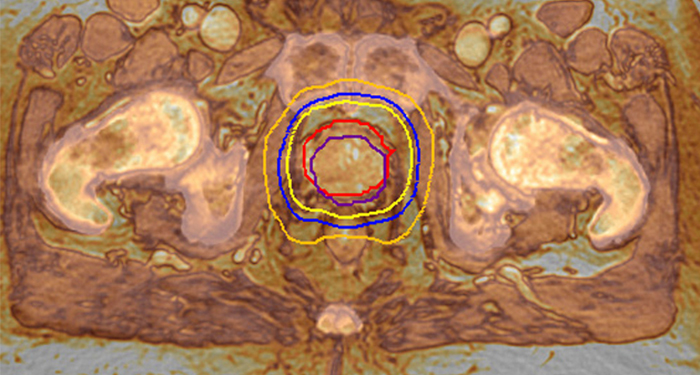

MRCAT Prostate + Auto-Contouring

Come applicazione clinica plug-in per Ingenia RM-RT, in appena 20 minuti la combinazione di MRCAT Prostate e Auto-Contouring offre mappe di attenuazione e contorni automatizzati basati su RM della prostata e degli organi a rischio, il tutto in un flusso di lavoro ripetibile con un solo clic.

MRCAT Pelvis consente di pianificare la radioterapia utilizzando esclusivamente la RM come unica soluzione. All'interno di un solo esame RM, MRAT Perlvis offre un livello eccellente di contrasto dei tessuti molli per il bersaglio e di delineazione degli OAR, nonché unità Hounsfield continue per i calcoli della dose. I dati MRCAT (acronimo di MR for Calculating ATtenuation, RM per attenuazione del calcolo) possono essere utilizzati per l'esportazione in sistemi di pianificazione del trattamento per calcoli della dose equivalenti alla TC**. Inoltre, l'imaging basato su RM consente il posizionamento basato su CBCT secondo un contrasto dei tessuti molli, dall'aspetto tipico della TC.